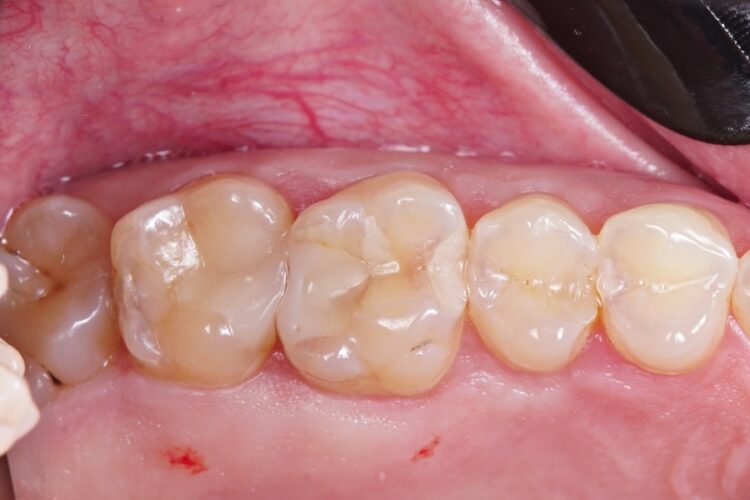

Пломбування жувальних зубів фотополімером

Пацієнт звернувся зі скаргою на постійне застрягання їжі між бічними зубами, та неприємний запах при чищенні зубною ниткою між ними. Було діагностовано неякісне прилягання старих пломб та вторинний карієс, що розвинувся під ними. Ми провели очищення зубів від старого матеріалу та каріозного ураження. Пломбування зубів проведено матеріалом ASTERIA, Tokuyama (Японія) з формуванням якісного та щільного контакту між ними.